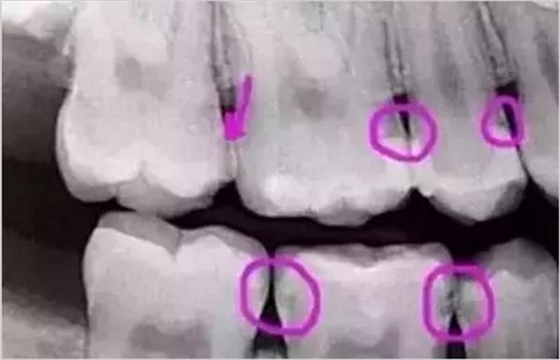

圈出來的地方或多或少都有點(diǎn)齲齒,但是有些你并不能看見。這些齲齒還淺不會讓你有什么感覺,頂多吃東西塞牙,和冷水敏感而已。